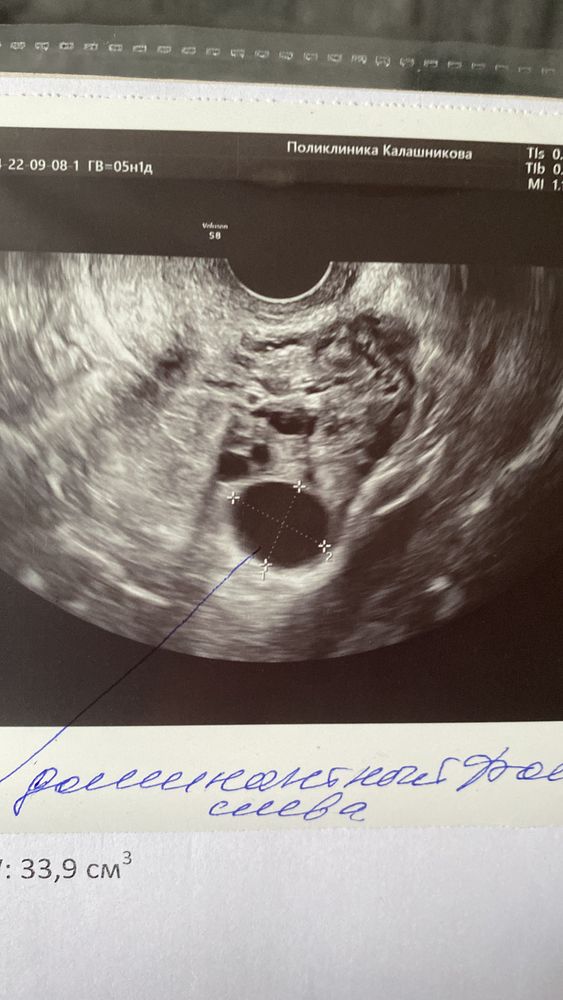

Думала уже что не растёт там ничего, пошла посмотреть исчезли или нет хотяб мои кисты после прошлой стимуляции а там дф 16,5*19*9🥹 сам вырос, мой родненький) долго мешкалась между тем колоть или нет хгч) утром тест на овуляцию был тусклый, сейчас же практически пик) решила ничего не колоть) т.к на двух стимуляциях в этом яичнике они не лопались с хгч.

и наращивать эндометрий 6мм такое у меня впервые..